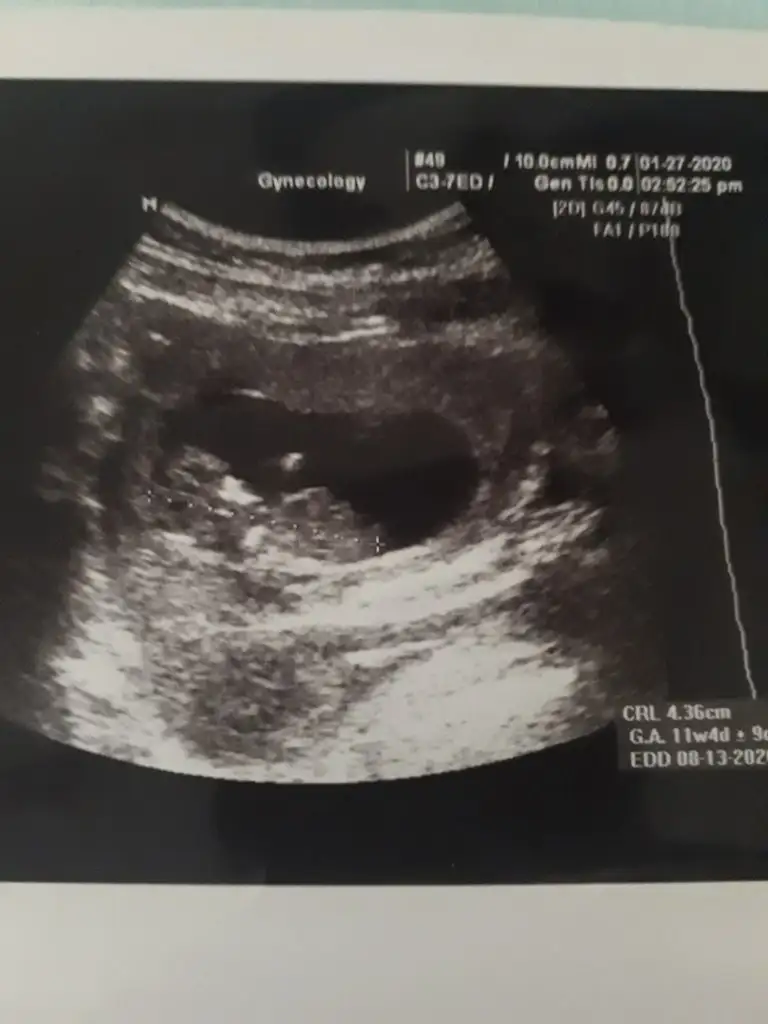

dr soylemeden siz gorun genital nub teorisi ( bebegin cinsiyeti)

Biraz daha belli olmuştur tekrar bakma şansınız olursa çok sevinirim 12.haftada dr hala erken dedi cinsiyet için

• 20200127_143851_001.webp

20200127_143851_001.webp

19,4 KB · Görüntüleme: 48